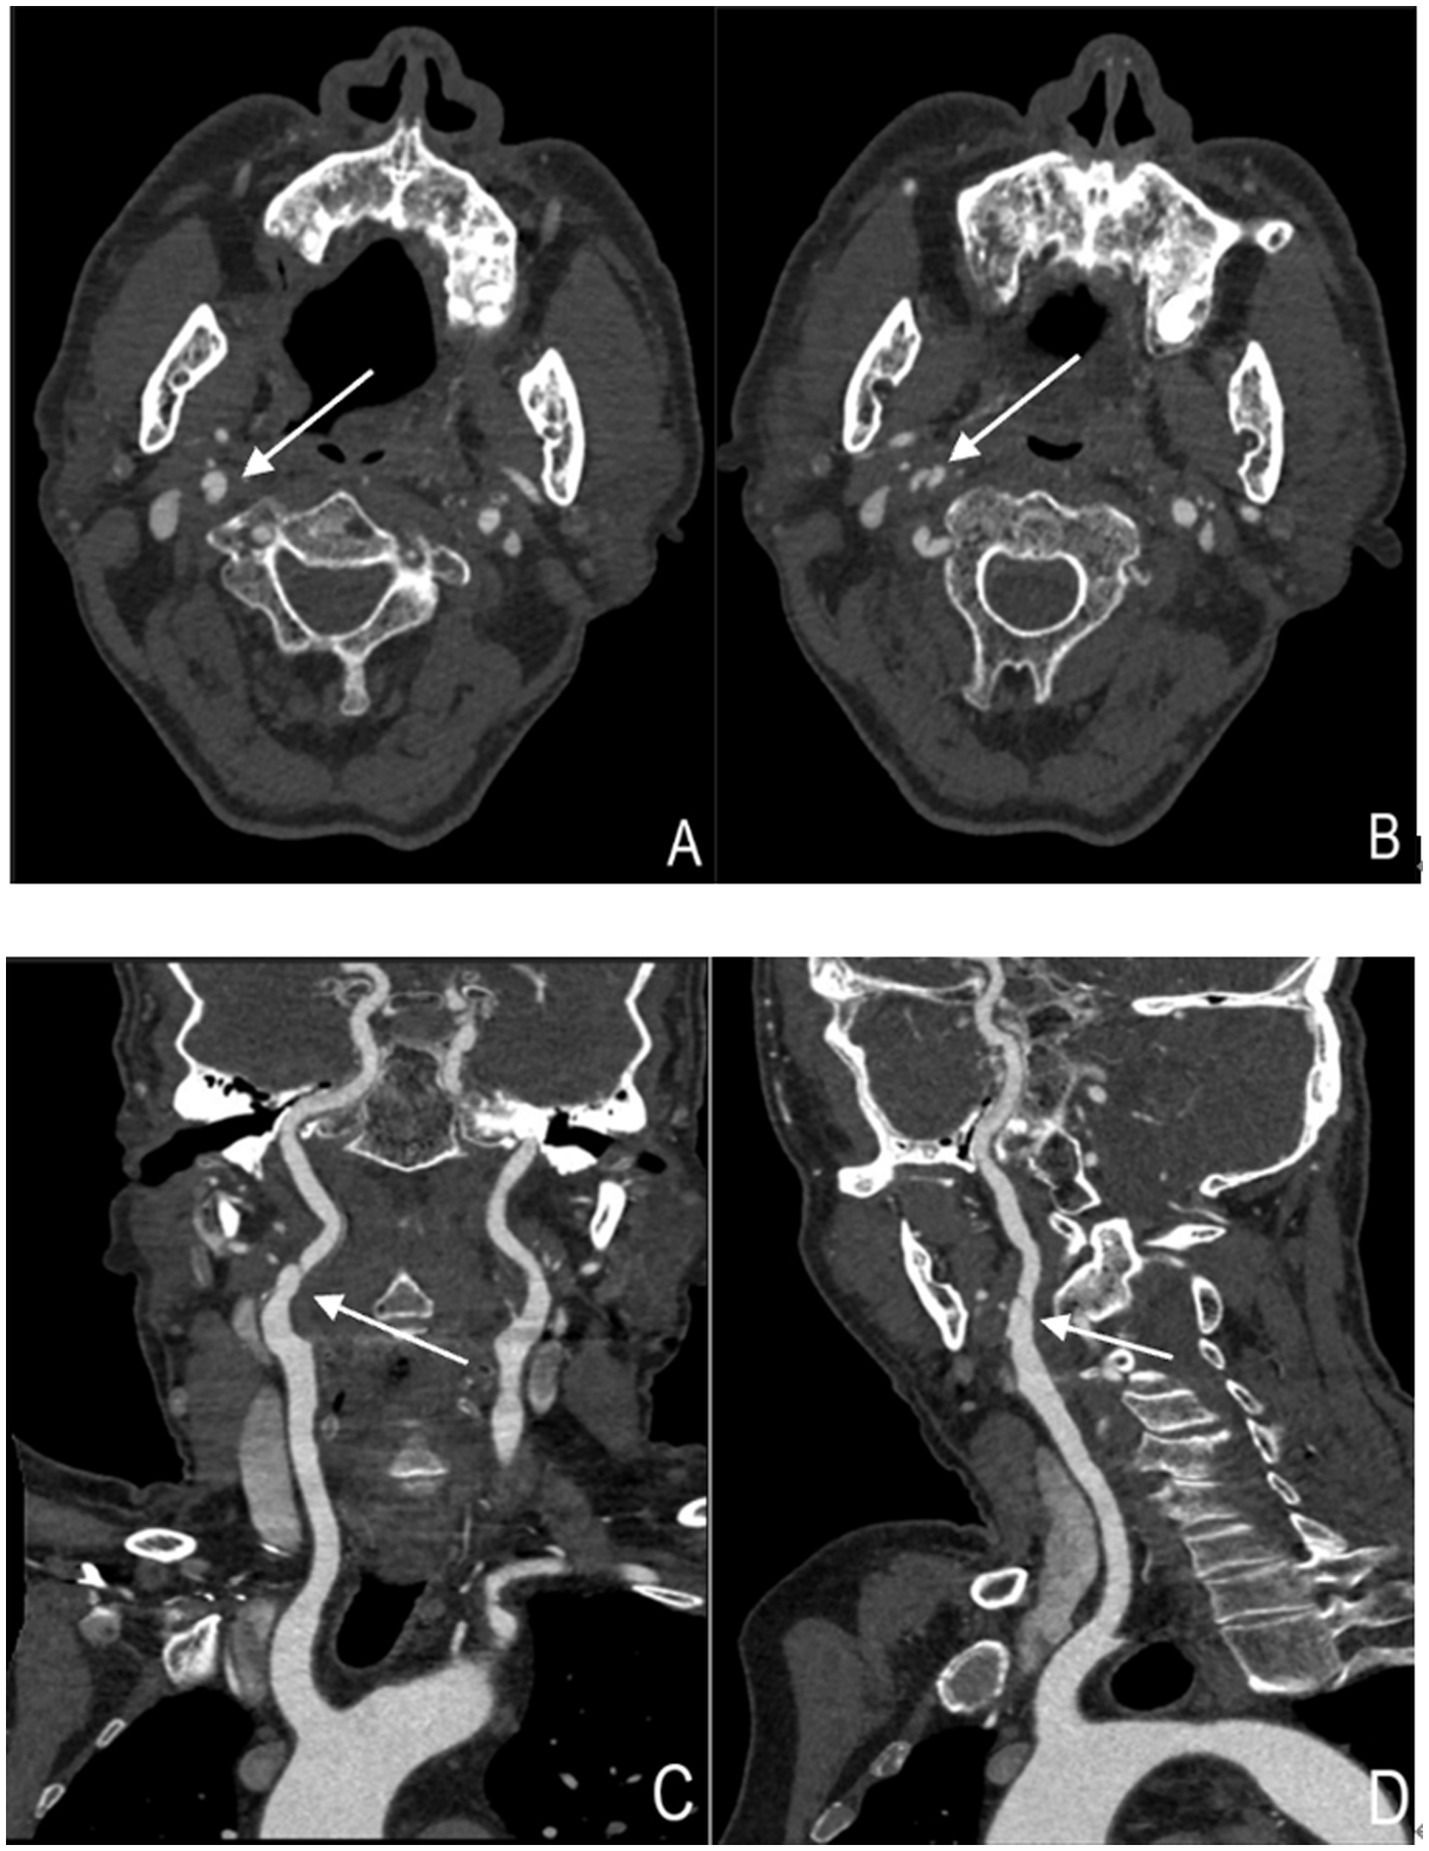

Cervical artery dissection has become one of the preferred imaging modalities for CAD diagnosis due to its rapid acquisition speed, high spatial resolution, and wide applicability (14). CTA demonstrates superiority over MRA in visualizing intimal flaps, dissecting aneurysms, and vascular lumen stenosis (15)(Figure 2).Particularly, the application of photon-counting CTA enables more precise depiction of dissection flaps, false lumens, and pseudoaneurysms (16). Given the smaller diameter of vertebral arteries and their proximity to cervical bony structures, CTA exhibits enhanced diagnostic performance for vertebral artery dissection (VAD) (17, 18), with sensitivity and specificity comparable to Digital subtraction angiography (DSA) (19). Furthermore, CT perfusion imaging (CTP) provides hemodynamic information about distal intracranial circulation in acute dissection cases, aiding patient selection for mechanical endovascular reperfusion therapy, leading to increasingly combined use of CTP with CTA in auxiliary diagnosis (12). The primary disadvantages of CTA involve radiation exposure and contrast agent administration, necessitating cautious use in patients with contrast allergies, renal insufficiency, as well as children and pregnant women (20). Additionally, inaccurate contrast injection timing and the presence of metallic implants can compromise image quality and diagnostic accuracy.

Figure 2

Cervical artery dissection showing arterial dissection-related vascular changes (right internal carotid artery). (A,B) Axial images of the right internal carotid artery. The structure indicated by the arrow represents the "double lumen sign," where the intimal flap divides the vascular lumen into two parts. (C,D) Coronal and sagittal images of the right internal carotid artery, respectively. The structure indicated by the arrow represents the "double lumen sign".